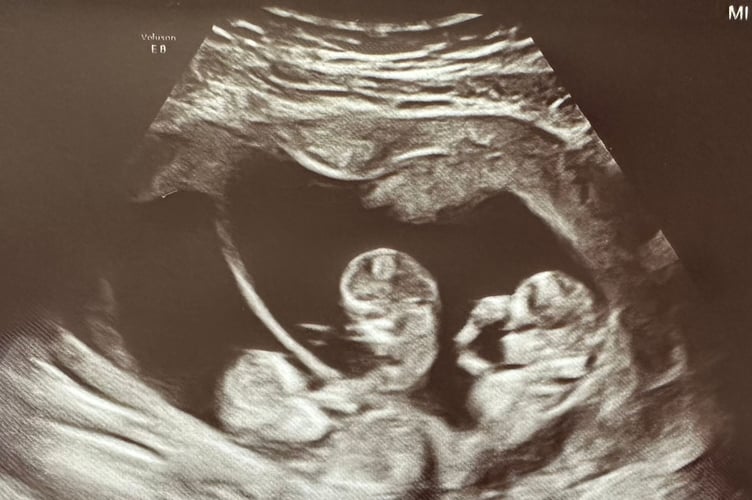

During the scan, the sonographer's hands started to shake and Hannah and Chris immediately thought the worst but she revealed the pair were expecting triplets.

Hannah said: "We didn't know what to expect at the scan - it felt like the specialist was taking ages.

"When the sonographer stopped she turned to us and she was shaking, we were expecting bad news.

"She had never been in the position before that she found triplets, it was a big moment for her and an even bigger moment for us.

"I had a nervous laugh, I started laughing right away. She turned to the screen and pointed out the different places where the babies were.

"I burst out crying, there were a lot of emotions."